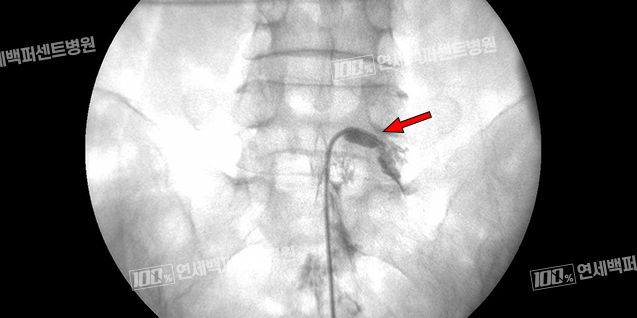

풍선 확장 경막외 신경성형술

꼬리뼈로 카테터를 삽입해 병변까지 도달시킨 뒤 카테터 끝에 달린 풍선을 확장해

협착부위를 넓히고 직접 염증 완화 및 유착방지 약물을 주입하는 시술입니다.

척추전방전위증

풍선확장술